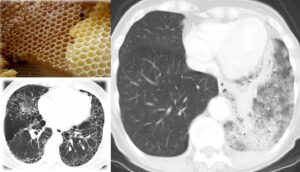

- Cluster sign: distribuzione segmentaria a grappolo

- Target sign: aspetto trilaminato con ipodensità centrale (necrosi), rim iperdenso (reazione flogistica di parete), vallo esterno ipodenso (edema perilesionale)